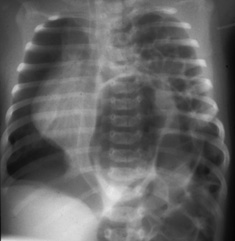

While on the pediatric surgery service, you are called to the neonatal intensive care unit to evaluate a thirty-six hour old infant. The infant is grunting on expiration, his nostrils are flaring with each respiration, his respiratory rate is 52 (normal = 30), and his oxygen saturation is 88%. Auscultation reveals an absence of breath sounds on the left side of his chest, but you note apparent bowel sounds on the left side of the chest. The patient has no bowel sounds within his abdomen. The resident orders a chest x-ray, which demonstrates bowel within the thorax . The x-ray confirms a diagnosis of a congenital diaphragmatic hernia. The patient has an endotracheal tube inserted and is placed on a ventilator. He ultimately requires additional respiratory support and is placed on an Extracorporeal Membrane Oxygenator (ECMO). The resident speaks with the family regarding the surgical repair which is necessary to repair the diaphragmatic hernia.